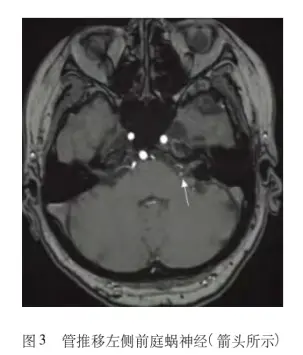

MRI:敏感性高,敏感性可高达60%甚至更高。

第八对颅神经受到血管压迫